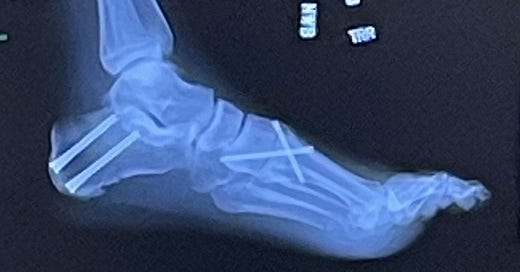

Re: One Picture is worth…. Just wanted to share an image of the exceptional body work of my mechanic…